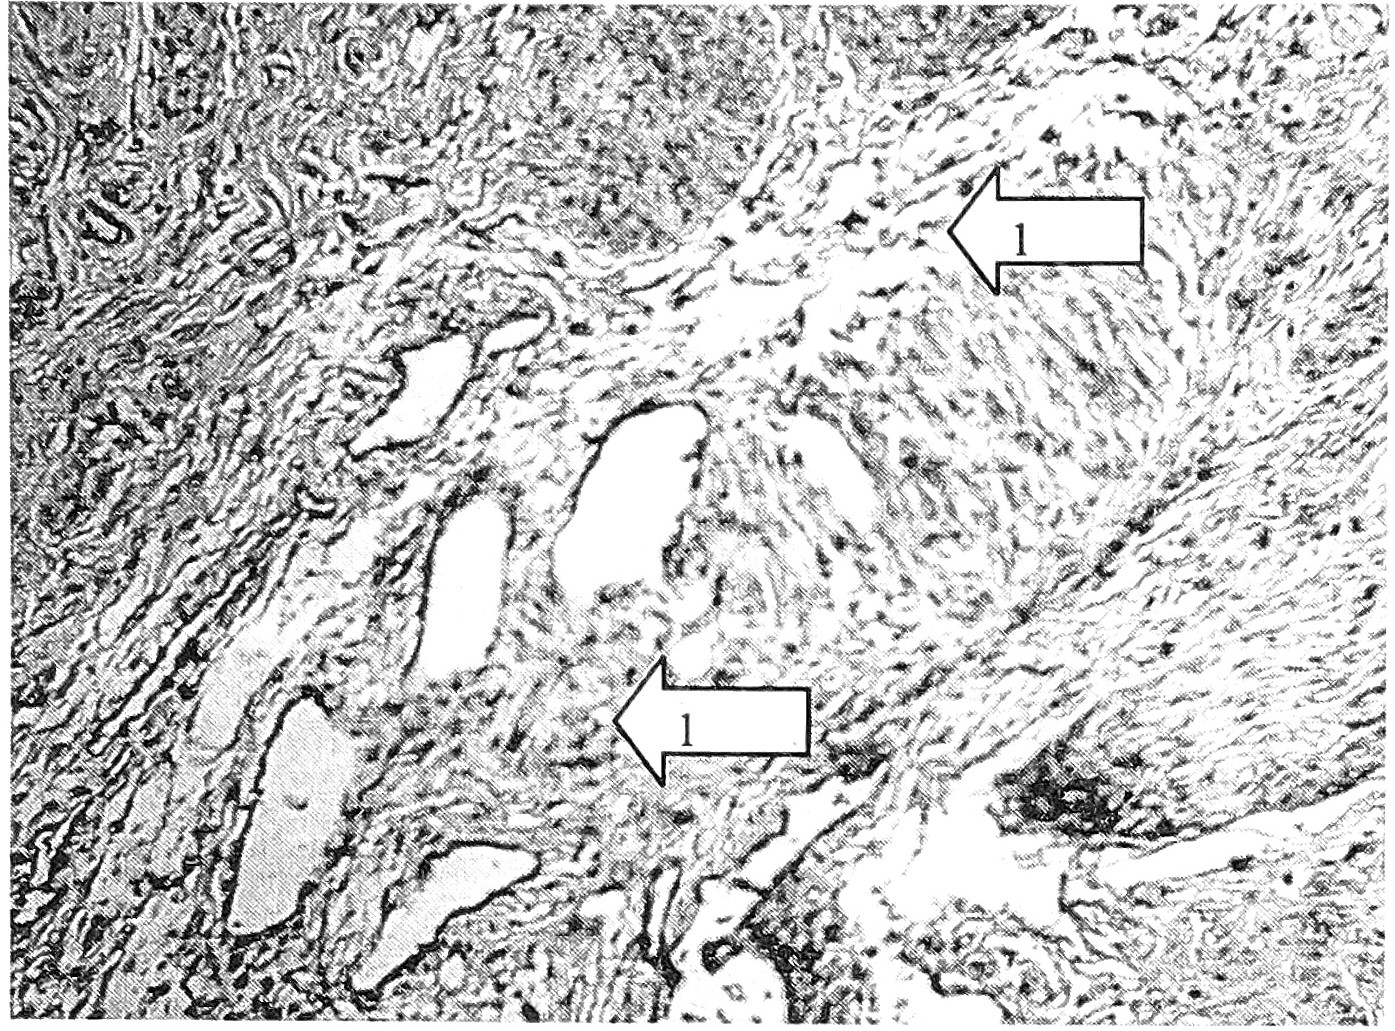

Рис. 1. Контрольное наблюдение (пациентка 45 лет). Слабо выраженная периваскулярная экспрессия коллагена I типа (1). Ув. 400.

В строме и стенках склерозированных артериальных сосудов с деформацией просвета происходит дезорганизация соединительной ткани, которая проявляется неравномерным мукоидным отеком, нарушением тинкториальных свойств коллагена, очаговым гиалинозом. В мышечных слоях наблюдается разрастание соединительной ткани вокруг и между пучками мышечной ткани, коллагенизация аргирофильных волокон между лейомиоцитами с их разобщением, сдавлением, смещением, атрофией мышечной ткани. Совокупность этих процессов приводит к нарушению архитектоники и соотношений мышечной и соединительной ткани. С этими процессами сочетается гипертрофия, набухание, фрагментация и уменьшение количества эластических волокон вокруг сосудов и мышечных пучков. Все описанные изменения варьируют в количественном и качественном отношении, но взаимосвязаны и коррелируют не столько с возрастом, сколько с давностью процесса и степенью ЭШМ. От инволютивных возрастных изменений их отличает значительное нарушение архитектоники тканевых структур, интенсивность и постоянство коллагенизации межмышечных аргирофильных волокон. Инволютивную природу исключает их постоянство и значительная выраженность у молодых женщин, не имеющих в анамнезе акушерской патологии, что подтверждает их причинно-следственную связь с ДСТ. Тем не менее это не исключает того, что закономерно нарастающие инволютивные процессы у женщин в менопаузальном и постменопаузальном периодах усугубляют прогрессирование ЭШМ, чем может объясняться больший, чем в группе больных в возрасте 29-45 лет, процент ЭШМ 2-3-й степени.

Характерно относительное снижение экспрессии антител к коллагену I типа в строме, стенках сосудов и повышение ее в пучках мышечных волокон и вокруг лейомиоцитов. В этих же структурах, как в поверхностных, так и в глубоких отделах шейки матки, повышаются и имеют распространенный характер экспрессируемые коллагены III и IV типов (рис. 1, 2, 3).